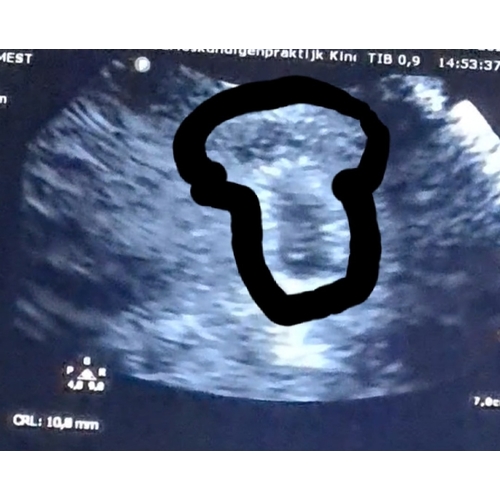

Lijkt mij niet dat het om een tweeling gaat.. Want ik zie geen vruchtzakje. Weet je zeker dat je het ziet kloppen en komt dat niet door het beeld van de echo?

Lijkt mij niet dat het om een tweeling gaat.. Want ik zie geen vruchtzakje. ...